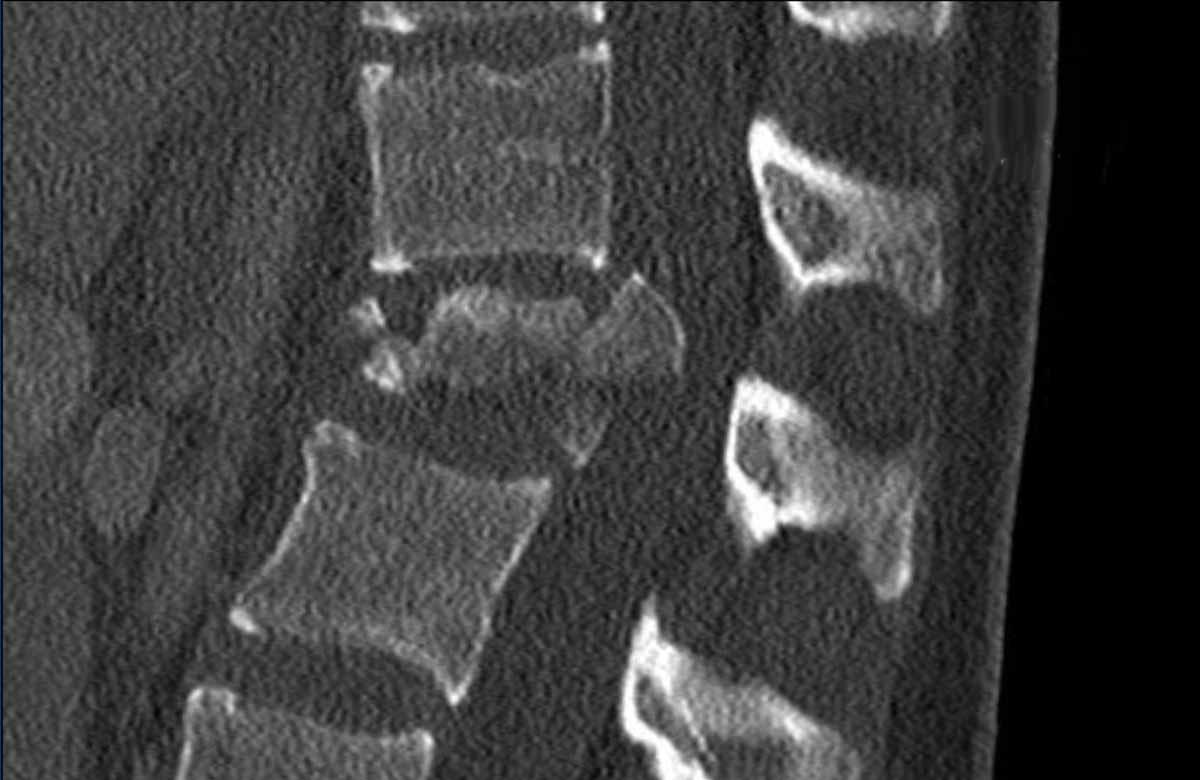

Findings

- The most severe level is L4/5 with dislocation (dotted lines)

- Facet fractures at L4 (arrows).

- A4 burst fracture (circle).

Conclusion:

Injury type C + A4 at L4/5.

Continue with the next stack of images to classify level L2…